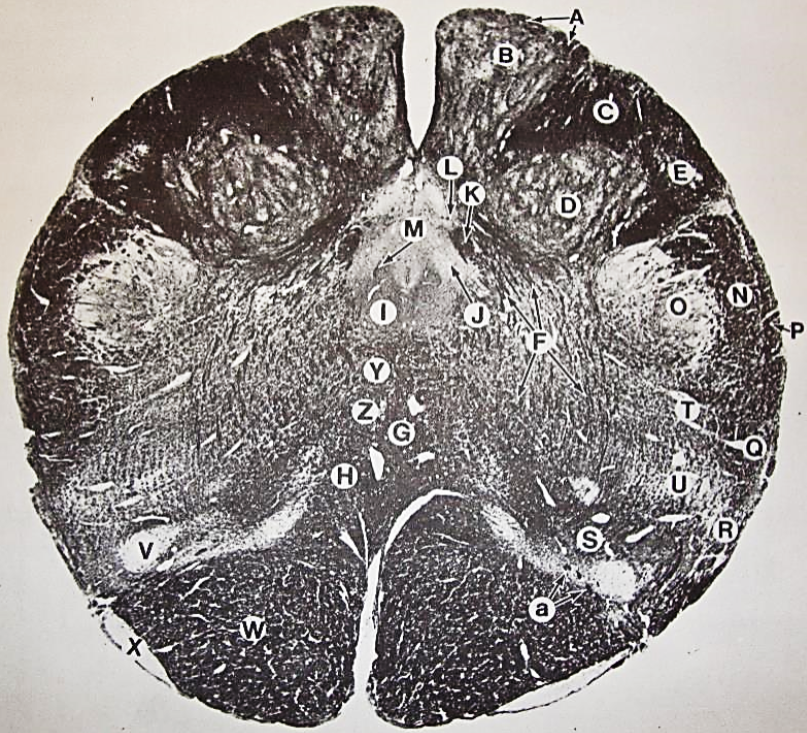

A

fasciculus gracilis

B

gracile nucleus

C

fasciculus cuneatus

D

cuneate nucleus

F

internal arcuate fibers

G

decussation of internal arcuate fibers

H

medial lemniscus

I

hypoglossal nucleus

J

dorsal motor nucleus vagus

K

solitary fasciculus

L

solitary nucleus

M

dorsal longitudinal fasciculus

N

spinal trigeminal tract

O

spinal trigeminal nucleus

P

posterior spinocerebellar tract

Q

anterior spinocerebellar tract

R

spinal lemniscus

S

lateral vestibulospinal tract

T

rubrospinal tract

U

lateral reticular nucleus

V

medial accessary olivary nucleus

W

pyramidal (corticospinal) tract

X

arcuate nucelus

Y

medial longitudinal fasciculus

Z

tectospinal tract

a

fascicles of hypoglossal nerve